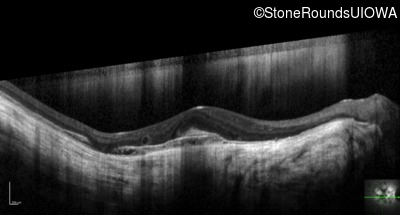

Optical Coherence Tomography - Right - 20/40 -2

Exemplar / OCT Stack

OCT Stack